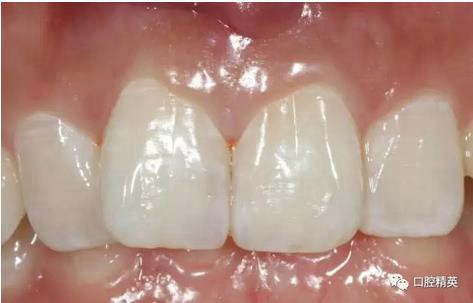

口內(nèi)正側(cè)位及切端特寫

從側(cè)位照可看出遠中切角略有回收

對比來看基本達到患者預期

有一點不足之處在于齦緣的高低不完全一致,補救辦法同上——激光輕掃